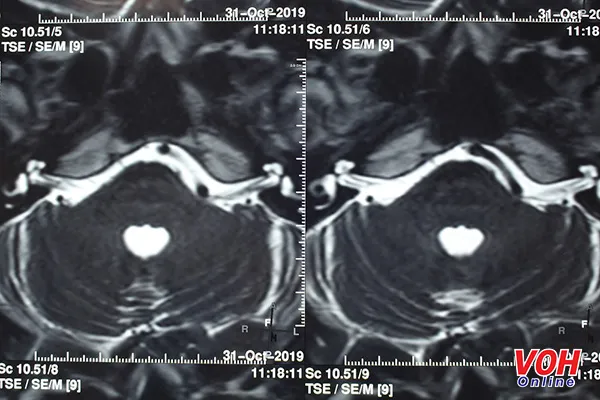

Hình ảnh qua MRI não phát hiện dây thần kinh số VII bên trái của bệnh nhân bị một mạch máu chèn ép